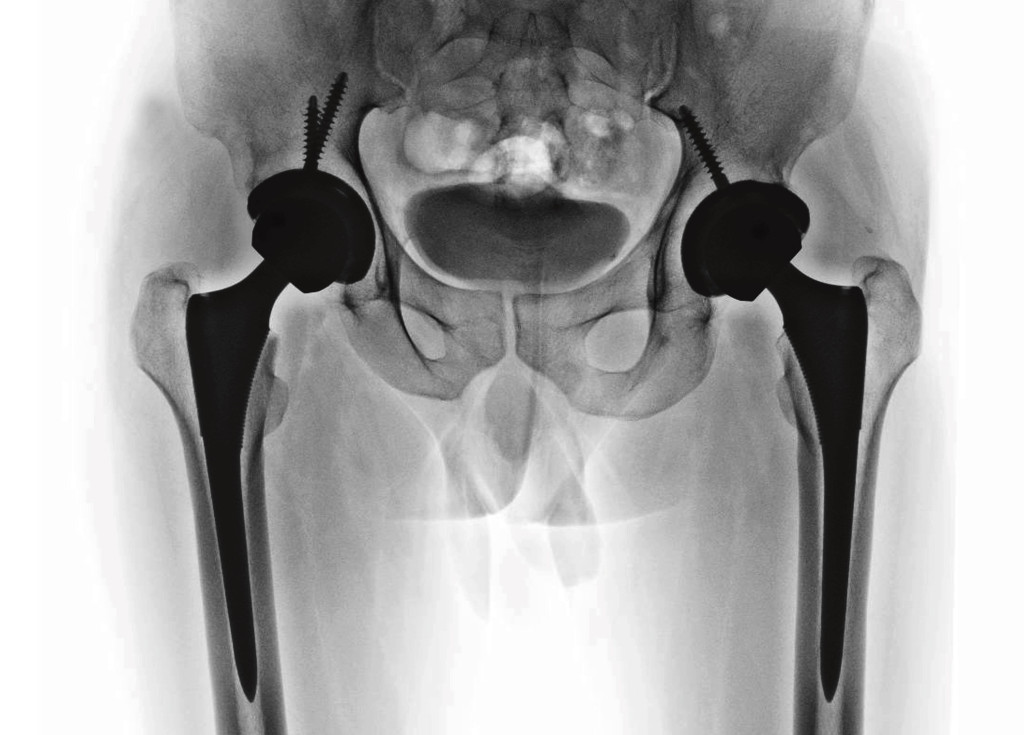

Illustrasjon: Sittithat Tangwitthayaphum / iStock